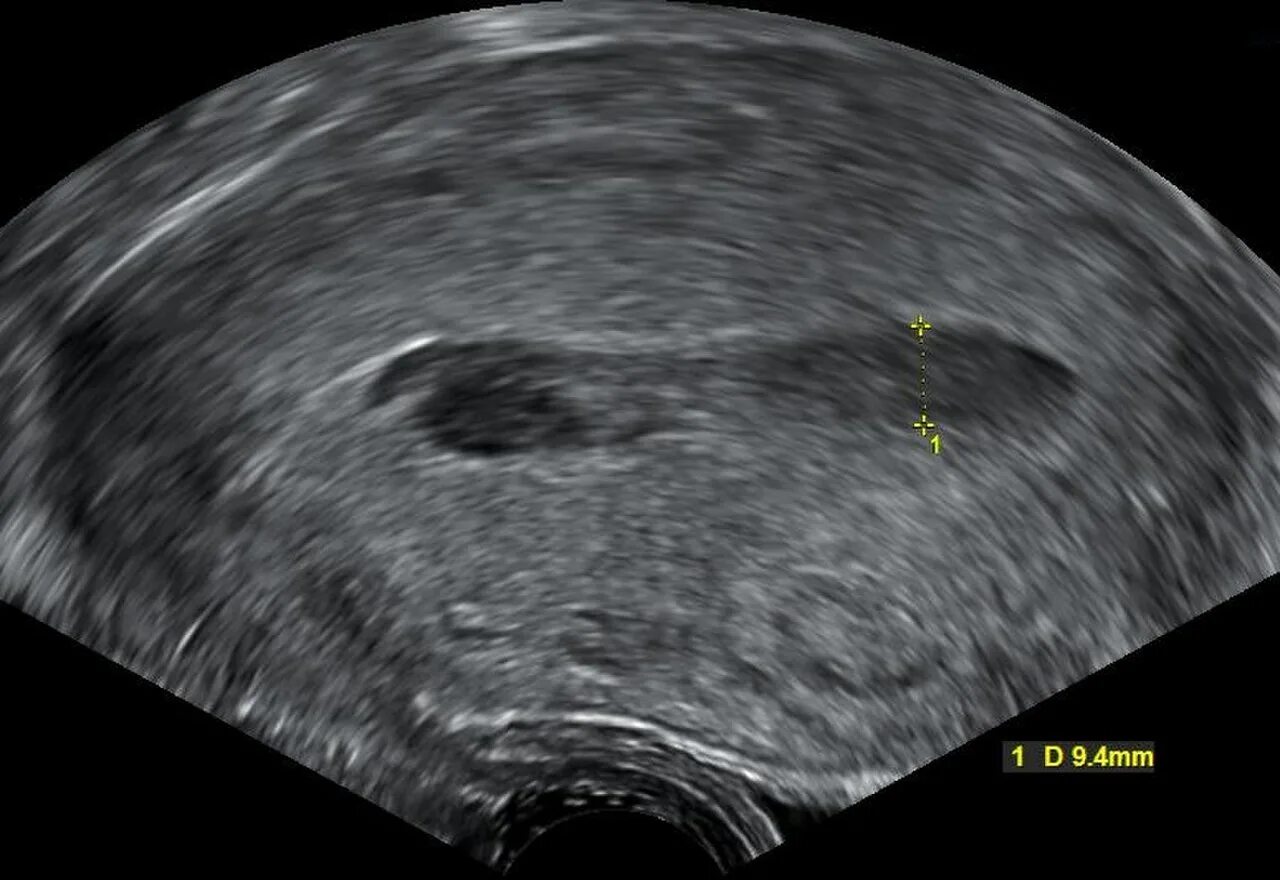

Гематометра симптомы